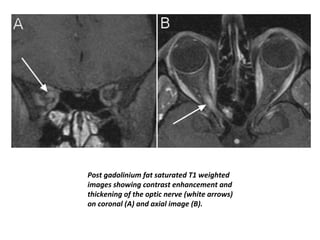

Post gadolinium fat saturated T1 weighted

images showing contrast enhancement and

thickening of the optic nerve (white arrows)

on coronal (A) and axial image (B).